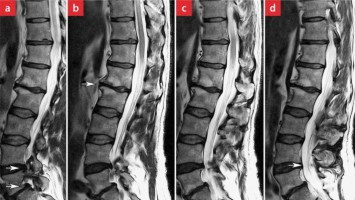

Beinschwäche bei einem Sportlehrer - Ihre Diagnose?

Ein 56-jähriger Sportlehrer berichtet, dass er seit dem Frühjahr Rückenschmerzen hat. Beim Radfahren spürt er keine Konditionsprobleme, doch beim Basketball merkt er, dass seine Beine unkoordinierter sind als früher. In letzter Zeit bekommt er häufiger Krämpfe in den Unterschenkeln und bemerkt eine Taubheit in der linken großen Zehe.

In Risikogebieten tragen circa 1–2 % der Zecken das FSME-Virus./© astendal / stock.adobe.com (Symbolbild mit Fotomodell), Ärztin erklärt Patient etwas auf Tablet/© SDI Productions / Getty Images / iStock (Symbolbild mit Fotomodellen), Sagittales T-2-gewichtetes MRT der LWS des Patienten/© Wolfgang Freund, Teaserbild - Entwicklungen in der Therapie neuromuskulärer Erkrankungen/© Dr_Microbe / stock.adobe.com, Schlafmittel/© terovesalainen / stock.adobe.com (Symbolbild mit Fotomodell), Hinter Albträumen und dem Ausagieren von Träumen kann eine REM-Schlaf-Verhaltensstörung stecken./© Vadym / stock.adobe.com (Symbolbild mit Fotomodell), Ärztin misst Frau den Blutdruck/© New Africa / stock.adobe.com (Symbolbild mit Fotomodellen), Die Elektromyografie ist essenziell für die (Differenzial-)Diagnostik bei Muskelschwäche./© romaset / Stock.adobe.com (Symbolbild mit Fotomodellen), Schwitzende Frau/© RapidEye / Getty Images / iStock (Symbolbild mit Fotomodell), Mann tippt auf Smartphone/© chinnarach / stock.adobe.com, Älter Patient im Klinikbett/© Yakobchuk Olena / stock.adobe.com (Symbolbild mit Fotomodellen), Frau mit schmerzendem Kiefer/© Adiano / stock.adobe.com (Symbolbild mit Fotomodell), Frau mit psychischen Problemen sucht Psychiater auf/© Serhii / Stock.adobe.com (Symbolbild mit Fotomodellen), Pantherpilz/© Mit freundlicher Genehmigung von Bettina Haberl, Apothekerin holt Arzneimittel aus Regal/© I Viewfinder / Stock.adobe.com (Symbolbild mit Fotomodell), Einweckglas mit Hering/© FoodieMedia / Getty Images / iStock (Symbolbild), Frau mit starken Gesichtsschmerzen/© pain au chocolat / stock.adobe.com (Symbolbild mit Fotomodell), Fußdystonie Parkinson/© W. Jost, Alter Mann liegt am Boden/© LIGHTFIELD STUDIOS / stock.adobe.com (Symbolbild mit Fotomodell), Schlafender Autofahrer/© EdNurg / stock.adobe.com (Symbolbild mit Fotomodell), Elektroenzephalogramm bei einem Kleinkind/© dblight / Getty Images / iStock (Symbolbild mit Fotomodell), Einem Mann wird Fieber gemessen/© eggeeggjiew / Getty Images / iStock (Symbolbild mit Fotomodell), Junge Ärztin vor einem Triage-Zelt/© Milos / Stock.adobe.com (Symbolbild mit Fotomodell), Kranker Junge mit erhöhter Temperatur/© Imgorthand / Getty Images / iStock (Symbolbild mit Fotomodell), Senior nimmt Medikament an/© Yuri Arcurs / Fotolia (Symbolbild mit Fotomodellen), Schwangere mit Medikament/© Stockbyte / Thinkstock (Symbolbild mit Fotomodell)